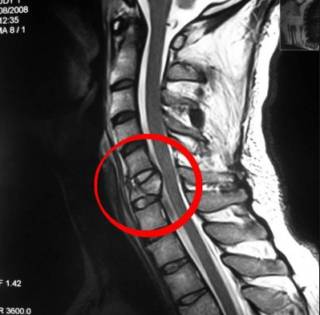

У многих хрустит позвоночник в шейном отделе при вращениях и наклонах головы. Это говорит о наличии отложений солей и деформации остистых отростков. Очень часто хруст в шее является первым тревожным сигналом о том, что происходит деформация каналов, через которые проходят задние позвоночные артерии. если у вас появился хруст в шейном отделе позвоночника, не ждите ухудшения своего состояния. Срочно обратитесь к мануальному терапевту. На ранней стадии это заболевание возможно вылечить без следа с помощью методик остеопатии, кинезитерапии, рефлексотерапии и лечебной гимнастики.

Хруст в шее может возникать при синдроме позвоночной артерии, а также при травмах и остеохондрозе. При патологии в пояснице нередко наблюдается грыжа позвоночника.

Если у человека при каждом прогибе хрустит позвоночник, следует обратиться к врачу и пройти осмотр, а затем и инструментальную диагностику:

- рентген и МРТ позвоночника – всех отделов;